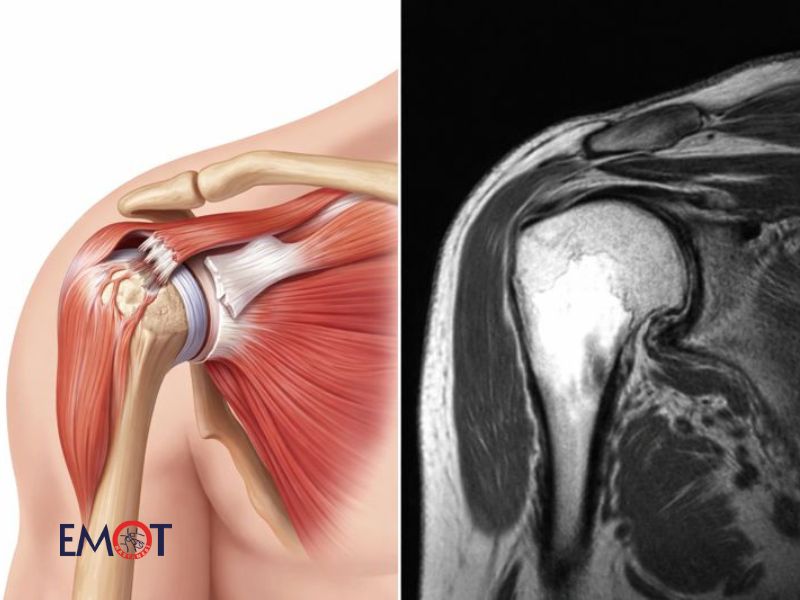

Omuz kas yırtığı, omuz ekleminin hareket kabiliyetini ve günlük yaşam kalitesini doğrudan etkileyen önemli bir kas-iskelet sistemi problemidir. Omuz, insan vücudunun en hareketli eklemlerinden biri olduğu için hem travmalara hem de zamanla gelişen dejeneratif süreçlere oldukça açıktır. Bu nedenle omuz kas yırtıkları, sporculardan masa başı çalışanlara kadar geniş bir hasta grubunda görülebilir ve çoğu zaman omuz hastalıkları içerisinde en sık karşılaşılan nedenlerden biridir.

Omuz kas yırtıkları genellikle rotator manşet adı verilen kas ve tendon grubunu etkiler. Bu yapı, omuz başının yuva içinde dengeli bir şekilde hareket etmesini sağlar. Kas yırtıkları, ani zorlanmalar sonucunda gelişebileceği gibi uzun yıllar boyunca tekrarlayan mikro travmalar ve yaşa bağlı yıpranmalar sonucunda da ortaya çıkabilir. Bu durum, hastalarda ağrı, hareket kısıtlılığı ve güç kaybı gibi şikâyetlere yol açar.